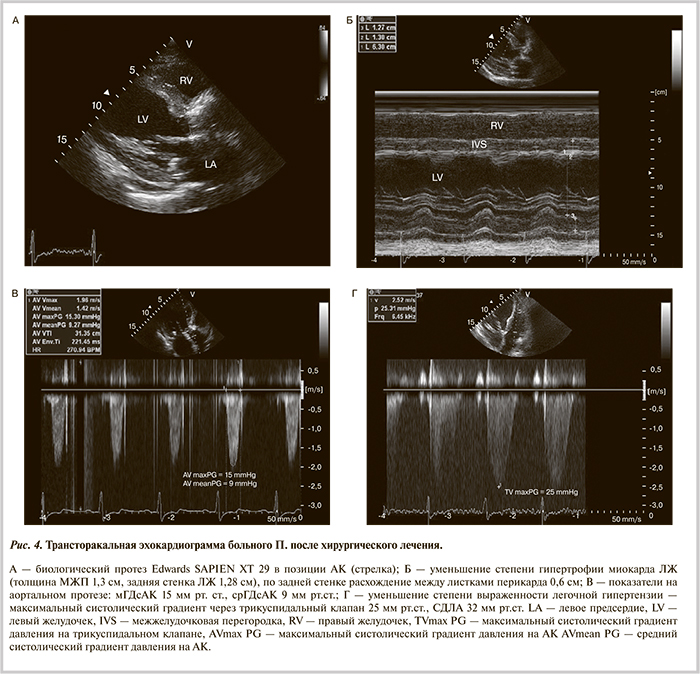

После хирургического вмешательства отмечено улучшение состояния больного: снижение ЧСС до 68—72 уд/мин, увеличение АД до 110—120/60 мм рт.ст., отсутствие одышки в покое и снижение давления в легочной артерии до 42/24 мм рт.ст. Успешное проведение малотравматичной операции без использования аппарата искусственного кровообращения позволило активизировать больного в течение 3 сут после операции. При повторном суточном мониторировании ЭКГ клинически значимых нарушений ритма и проводимости сердца не зарегистрировано. При ЭхоКГ на 3-и сутки после ТПАК (рис. 4) дисфункции аортального протеза не наблюдалось, уменьшились признаки легочной гипертензии и количество жидкости в полости перикарда.

От терапии варфарином решено было воздержаться, к проводимому лечению АСК, β-адреноблокаторами, малыми дозами ингибиторов ангиотензинпревращающего фермента, петлевыми диуретиками, антагонистами минералокортикоидных рецепторов, аторвастатином был добавлен клопидогрел. Наблюдались дальнейшая стабилизация состояния и параметров гемодинамики, уменьшение явлений недостаточности кровообращения со снижением уровня BNP до 440 пг/мл.